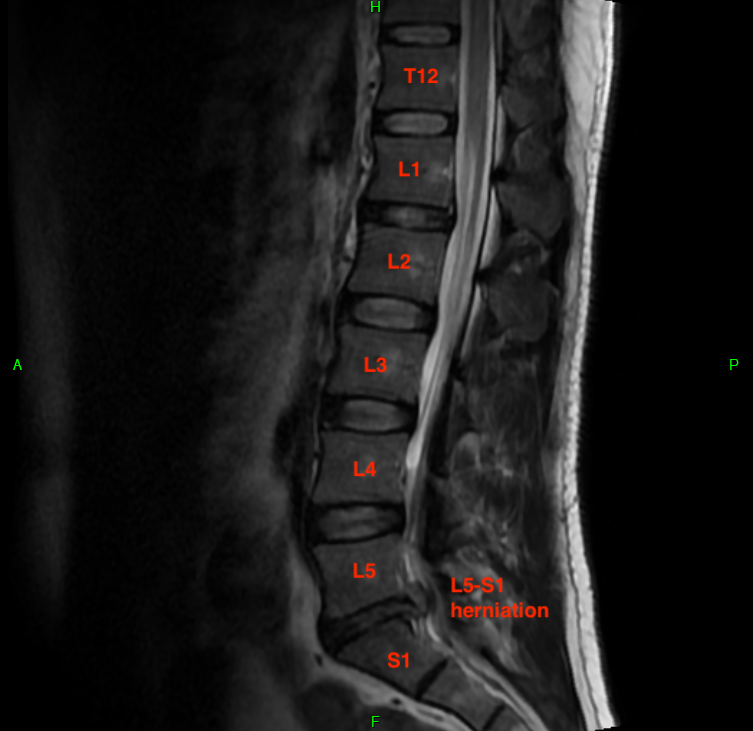

When taking MRIs, it's useful to correlate the sagittal (side) and axial (top) views. Imagine lying down and having a butcher slice you from right to left (sagittal) or from top to bottom (axial). The software that doctors use to examine MRIs is really cool in that you can scroll the mouse wheel on one diagram and it will show you your position on the correlated diagram. My MRI report listed a ton of deficiencies, most of which were minor issues that don't relate to my acute problem. This was the radiologist being diligent.

I want to show three levels for comparison. These are disc-level slices of my L3-L4 IVD, which is healthy. I've drawn cut lines on each image to show you how the slices correlate. These are T2-weighted images, which means water is hypersensitive (bright white). Tissue with high water content shows up as lighter, and you can see my relatively healthy IVDs all have a light center. That's because the nucleus pulposus is about 80% water and is responsible for about 80% of the axial load bearing of the spine. The remaining 20% of axial load is absorbed by the facet joints, which are a pair of hinge-like joints connecting adjacent vertebrae. They "fasten" the spine together and prevent excessive bending and twisting.

In the sagittal image, notice the bright white column just behind the vertebrae. This is the thecal (or dural) sac, which is the protective cavity for the spinal cord and cauda equina. In most adults, the spinal cord originates from the brain and terminates towards the end of the thoracic spine (T12) or around the beginning of the lumbar spine (L1). The spinal cord is quite thick and consumes much of the space inside the thecal sac. Mine ends at T12, so from there on down is the cauda equina, or "horse tail" of nerve endings. The thecal sac is still pretty wide despite only a handful of nerves passing through it, which makes it somewhat tolerant of encroachment from IVD herniations.

(Sagittal MRI)